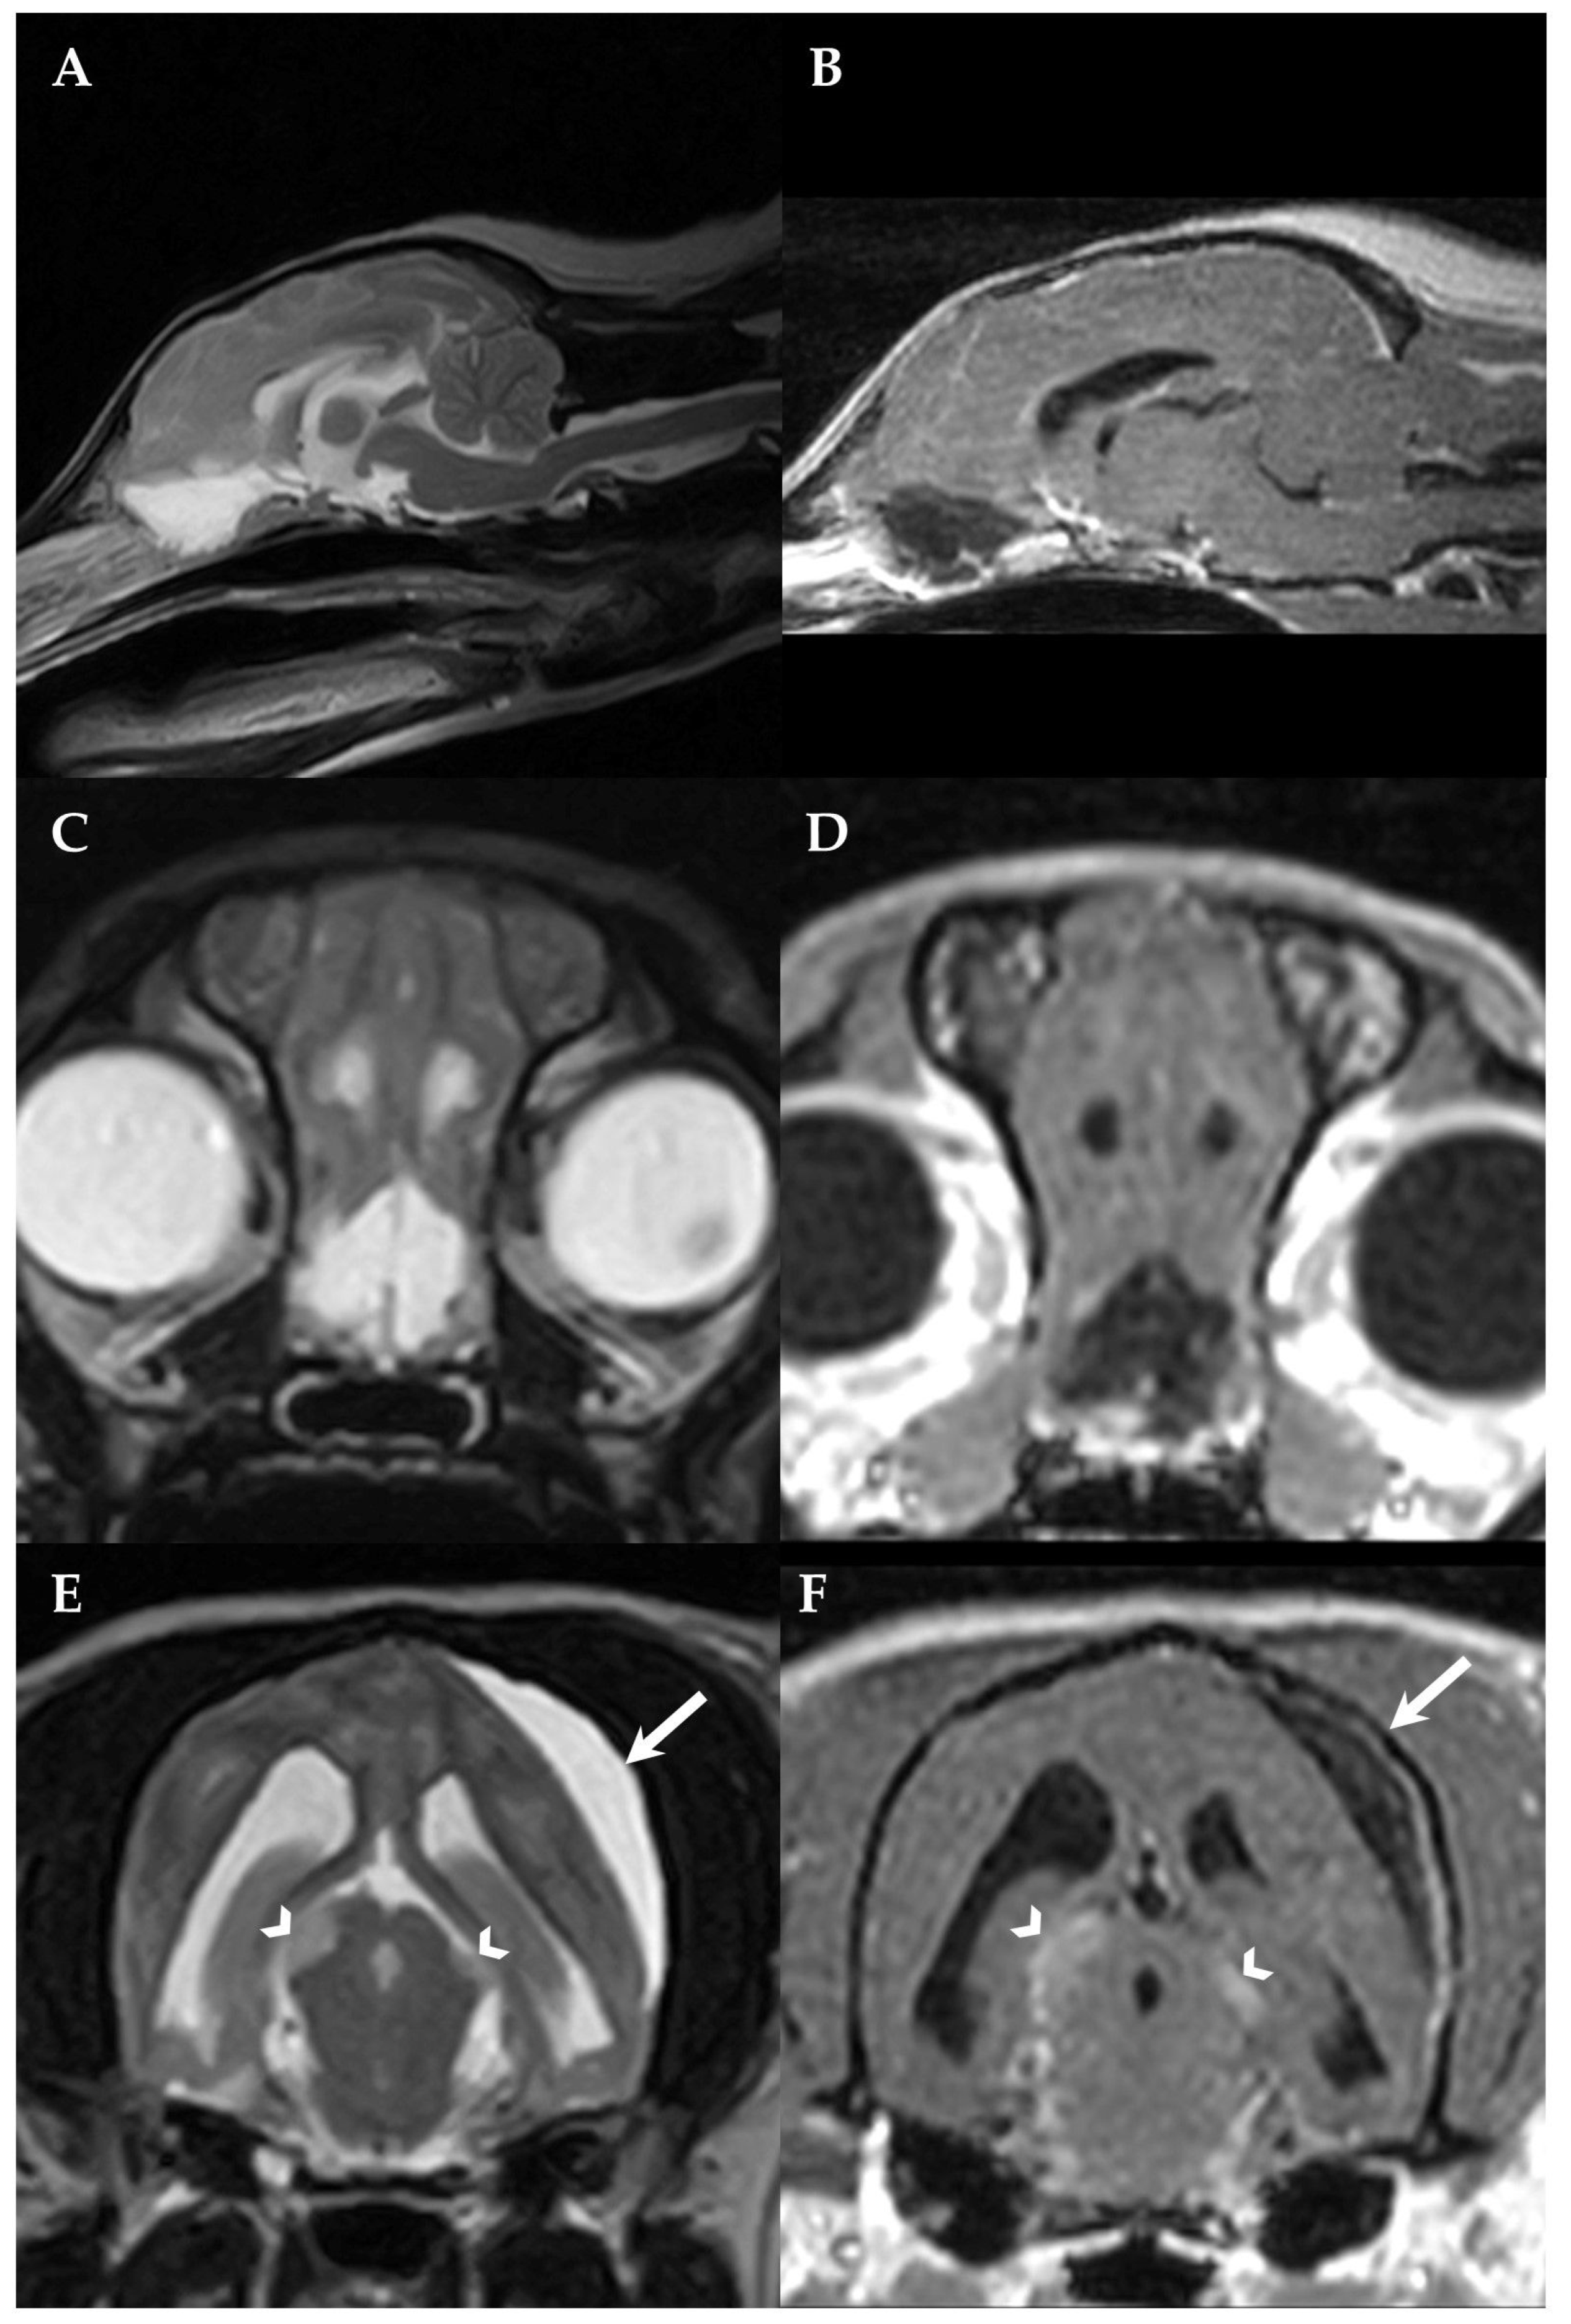

2. Case Presentation